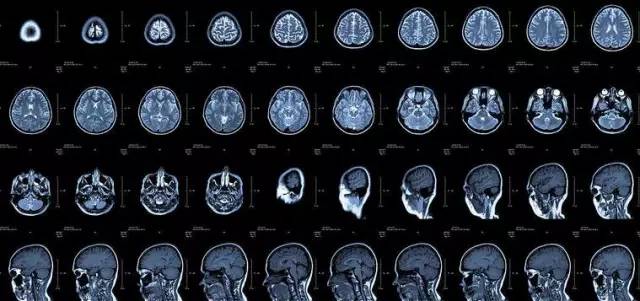

核磁共振

摇一摇再看

核磁共振机使用较强大的磁场 , 使人体中所有水分子磁场的磁力线方向一致 , 这时磁共振机的磁场突然消失 , 身体中水分子的磁力线方向 , 突然恢复到原来随意排列的状态 。 简单说 , 就相当于用手摇一摇 , 让水分子振动起来 , 再平静下来 , 感受一下里面的振动 。 所以 , 核磁共振也被戏说为是摇摇看的检查 。